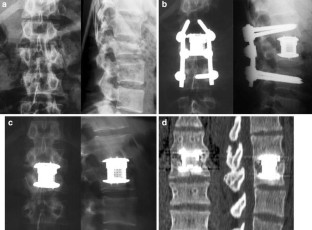

In the operative treatment of spinal injuries, the reconstruction of the anterior column of the thoracolumbar spine is still controversial. We conducted a prospective clinical study to investigate the clinical and radiological outcome of 50 patients treated with a vertebral body replacement of adjustable height (Synex™). Fifty consecutive patients were evaluated during in-patient treatment and at 12 and 20 months post-operatively in clinical notes and radiographs. 38/50 patients were operated for traumatic fractures. Out of 50 patients 45 attended the follow-up clinic 1 year post-operatively and 39 of these patients were examined after 20 months. Twenty-five patients returned to pre-injury activities within 1 year. This number increased to 29/39 patients at 20 months. Seventy-three percent of the patients returned to their job. After 1 year 25/45 patients complained of little or no back pain and 6 months later six patients were limited in their back function. At 1 year only three patients complained of surgical site pain which was improved at their final follow-up at 20 months. Individual satisfaction was determined using a score on a visual analog scale containing 19 questions on back pain, and functional limitation of the spine that has to be filled in by the patients at three different points of time. The score decreased from 87/100 pre-operatively to 65/100 at 1 year follow-up (P<0.001). The average permanent correction of the injured vertebra was 16.8° (88%) including 2.3° (12%) loss of correction at 12 months after operation. Bony integration was obtained in 83%. Early and intermediate outcome with the Synex™ vertebral replacement device for reconstruction of the anterior column appears promising. The loss of correction or reduction was only minimal. On the basis of our results we recommend the Synex™ implant as an alternative for the fixation and stabilisation of thoracolumbar fractures. However, long-term results and a clinically random control study are still required.